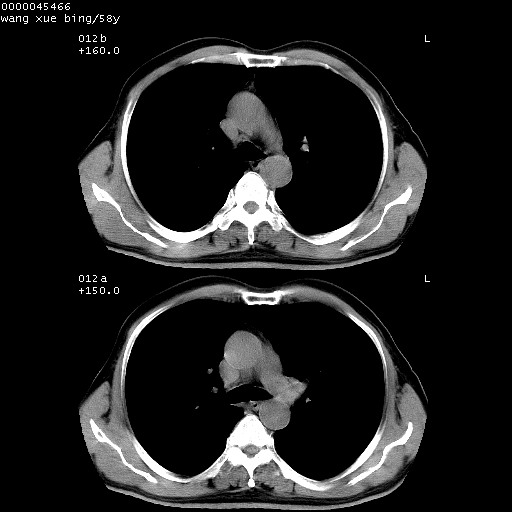

患者 男,58岁。咳嗽、咯血3月余。

胸部ct轴位平扫(层厚10mm,螺距1.5,重建间隔10mm),图像如下:

右肺下叶团块及不规则空洞,内壁不规则,外缘见粗长毛刺,临近胸膜明显增厚并与病灶关系密切。支持考虑:右肺肺脓肿!建议穿刺病理检查待除外周围型肺癌!

右肺下叶见不规则厚壁空洞,内壁不规则,外缘见粗长毛刺,临近胸膜明显增厚并与病灶关系密切。支持考虑:周围型肺癌!

右肺下叶周围型肺癌伴空洞形成!征象比较明显!分叶、毛刺、胸膜凹陷征、厚壁空洞,壁结节!

空洞壁厚,不规则,其内可见壁结节,周围可见毛刺及阻塞性炎变,多考虑癌性病变.

支持癌性空洞并远端阻塞性炎症

空洞内壁不规整,有壁结节,周围有毛刺,支持癌性空洞。